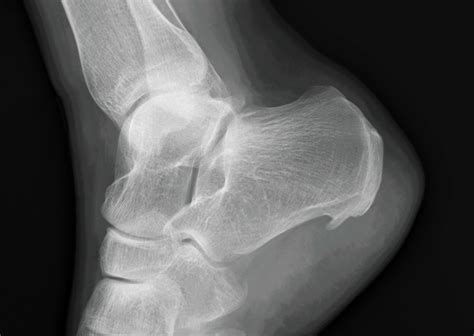

A heel spur, technically known as a calcaneal spur, is a bony protrusion that develops on the underside of the heel bone. Over time, calcium deposits build up on the heel, resulting in this outgrowth. These spurs are often associated with plantar fasciitis, a common condition that involves inflammation of the tissue running along the bottom of the foot.

It is important to note that many individuals possess heel spurs without ever experiencing any pain. The pain often stems not from the spur itself, but from the associated inflammation of the soft tissues surrounding the heel bone. This is precisely why a Heel Spur X Ray is ordered—to visualize the bone structure and help the physician determine whether the spur is the primary culprit or if other factors are contributing to your symptoms.

• Visualization: It provides a clear, high-contrast view of the heel bone, allowing the doctor to see the exact size and location of any bony growth.

Once the radiologist examines your Heel Spur X Ray, they will generate a report for your doctor. It is common for the report to confirm the presence of a "calcaneal spur." However, as mentioned previously, this does not automatically mean the spur is causing your pain. Your physician will correlate these findings with your physical symptoms. For instance, if your pain is worst in the morning or after long periods of sitting, the clinical focus will likely remain on treating the underlying plantar fasciitis, even if a spur is visible.